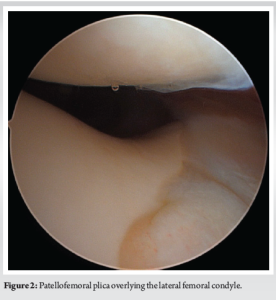

Diagnostic arthroscopy was performed secondary to pain, mechanical symptoms, and the diagnosis of a bucket-handle meniscus tear. Entry into the patellofemoral compartment revealed a large suprapatellar plica in contact with the lateral femoral condyle (Fig. 2). Within the medial compartment, diagnostic arthroscopy revealed the anomalous connection between the anterior and posterior horns (Fig. 3 and 4) and a radial tear at the posterior meniscus. The anomalous band was clearly a distinct structure from the medial meniscus with probing and became entrapped upon full extension of the knee. The band specifically ran from the posterior horn of the medial meniscus, superiorly, along the PCL, and ultimately attached to the anterior horn of the medial meniscus in an “O” shape. No chondral pathology was detected. A partial meniscectomy was performed to address the posterior radial tear located in the white–white zone, followed by debridement and removal of the anomalous attachment (Fig. 5 and 6).

Anomalies of the medial meniscus are uncommon compared to anomalies of the lateral meniscus, and they include discoid variants, hypoplasia of the anterior horn, and anomalous insertion of the anterior horn [13]. There have been limited case studies published involving anomalies of the posterior horn of the medial meniscus. One case describes a fibro-cartilaginous fold that covers the medial femoral condyle (but reports a normal posterior horn), and another case describes a fibrous band arising from the posterior horn, connecting it to the ACL [16,17]. Mariani et al. reported the first published case involving a combined anomaly of the posterior and anterior roots of the medial meniscus [13]. However, this case did not describe an anomalous connection between the horns, forming an “O” shape, and mimicking a bucket handle tear. Most reported anomalies of the medial meniscus involve insertion into the ACL, not the PCL. The overall prevalence of anomalous insertion of the medial meniscus into the ACL is 1.2–2.3%[18]. Due to the relatively high prevalence of this morphology, a classification system exists that breaks down anomalous insertion of the medial meniscus into the ACL. These three distinct subcategories are based on insertion location and include: Type 1 (into the lower portion), type 2 (into the middle portion), and type 3 (into the proximal portion; intercondylar notch), with type 2 being the most common [19]. A medial discoid meniscus was first described in 1941, about 50 years after a lateral discoid meniscus was first described by Tachibana in 1889 [20]. Since discoid menisci became a topic of research, it became abundantly clear that a lateral discoid meniscus is significantly more common than the rare medial discoid meniscus. In 10,000 meniscectomies performed by Smillie, 467 had a lateral discoid meniscus compared to just those that had a medial discoid meniscus[21]. Furthermore, in 14,731 menisci examined by Dickason et al., 10 of 8,040 (0.12%) medial menisci were discoid, whereas 102 of 6,691 (1.5%) lateral menisci were discoid [22]. Some controversy still exists regarding the pathogenesis of discoid menisci: Two predominant existing theories are Smillie’s embryological theory and Kaplan’s developmental and biomechanical hypothesis [23]. Smillie posited that a discoid meniscus is a result of an arrest in the normal development of the meniscus during embryogenesis [21,24]. Kaplan, on the other hand, proposed that abnormal mechanical forces during knee development could lead to the persistence of the discoid shape [25]. This hypothesis is supported by the observation that the lateral meniscus, which is more frequently affected by the discoid variant, covers a larger surface area of the tibial plateau during fetal development, making it more susceptible to abnormal mechanical stresses [24,25]. Given that medial discoid menisci are extremely rare, only small case series have been published in the literature. Our case, however, differs from all described anomalies in the literature as the meniscal band arising from the posterior horn of the medial meniscus connected to the anterior horn of the medial meniscus, thereby forming an “O” shape. A musculoskeletal 162 radiologist and fellowship-trained sports medicine orthopedic surgeon identified the pathology on MRI as a bucket-handle medial meniscus tear. There is literature that describes the MRI appearance of an anomalous insertion of the medial meniscus into the ACL, where there is a low signal intensity band that goes from the anterior horn of the medial meniscus, covering the ACL, and into the intercondylar notch [19,26]. That appearance, however, does not mimic that of a bucket-handle meniscus tear. The MRI appearance of our patient’s knee was likely complicated by the fact that there was an anomalous connection between the anterior and posterior roots of the medial meniscus, which appeared like a flipped meniscal fragment. An interesting aspect of this case was the lack of mechanical or painful symptoms present before the kneeling event, despite the anomalous meniscus still existing in the patient’s knee. It is very possible that this one event caused a mechanical disturbance of the anomalous tissue, displacing it into a position it was not in before the kneeling event, thereby causing new symptoms. However, it is not completely known why this one kneeling event precipitated symptoms. Finally, a large patellofemoral plica overlying the lateral femoral condyle was identified intraoperatively. This may have been an incidental finding but could have contributed as a source of pain. It also could have a potential association with the anomalous meniscus. However, there is no literature identifying an association between an anomalous medial meniscus and patellofemoral plica. Further investigation into this possible association is warranted.